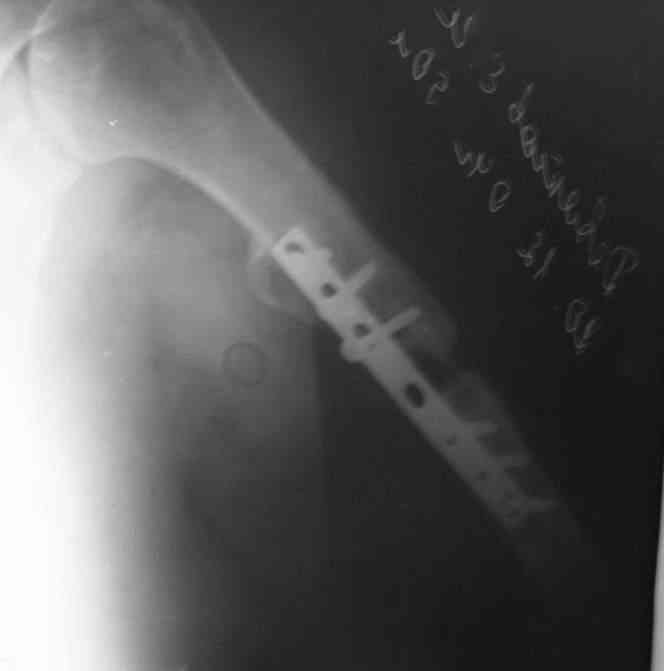

Есть вариант открытого вмешательства с резекцией зоны ложного сустава, костной пластикой и накостным остеосинтезом хорошей пластиной, в смысле мощной и длинной.

>A.Ch< Есть вариант открытого вмешательства с резекцией зоны ложного сустава, костной пластикой и накостным остеосинтезом хорошей пластиной, в смысле мощной и длинной.

Вряд ли для больной с ожирением и астмой большая травматичная операция с большим риском вослеоперационной нейропатии лучевого нерва является лучшим выходом...